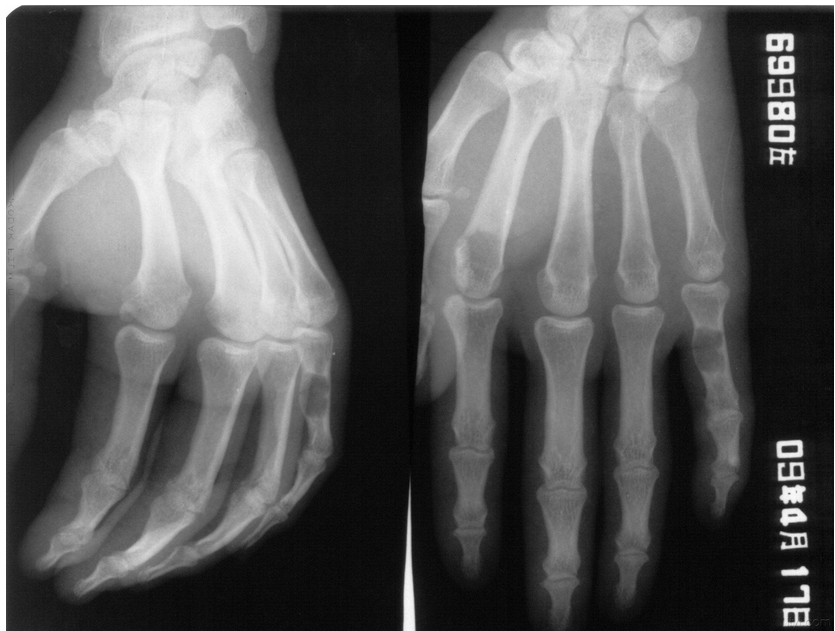

江西省医学科学院附属嘉佑曙光医院的医师介绍:骨外伤线可呈横行、斜形、螺旋形等。骨外伤的形态不同,稳定性也不同。无移位骨折、嵌插骨折及横形骨折复位后不容易再移位,为稳定性骨折。斜形骨折、螺旋形骨外伤及粉碎性骨折不容易固定,为不稳定骨折。